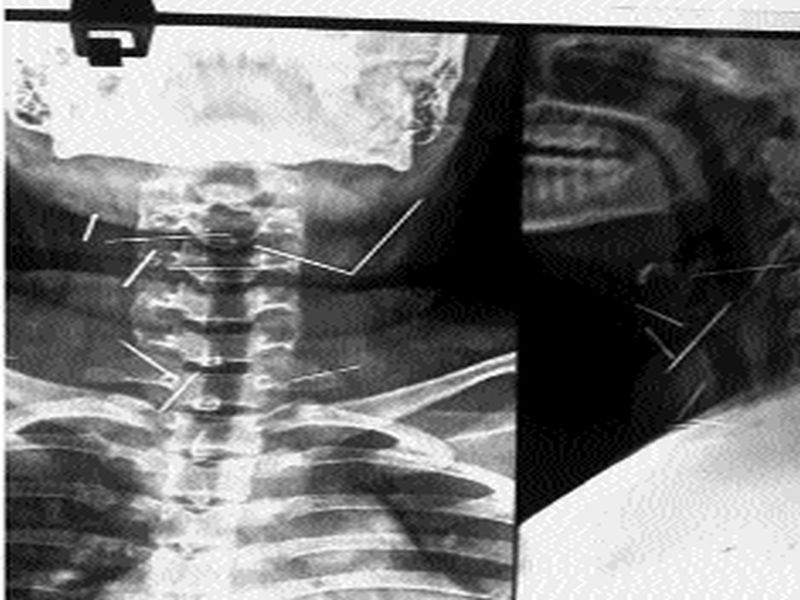

येथील निल रतन सरकार सरकारी इस्पितळातील डॉक्टरांनी एका १४ वर्षांच्या मुलीवर चार तास शस्त्रक्रिया करून तिच्या घशात अडकलेल्या नऊ सुया काढल्या.

कोलकाता : येथील निल रतन सरकार सरकारी इस्पितळातील डॉक्टरांनी एका १४ वर्षांच्या मुलीवर चार तास शस्त्रक्रिया करून तिच्या घशात अडकलेल्या नऊ सुया काढल्या.

अपरुपा बिश्वास नावाची ही मुलगी मुळची कृष्णनगरमधील असून मंगळवारी तिच्यावर शस्त्र्रक्रिया करण्यात आली. सुया गिळल्यामुळे तिच्या घशात अडकलेल्या नव्हत्या. तर बाहेरून टोचलेल्या सुया मोडून मांसल भागात अडकल्या होत्या. इस्पितळाचे ‘ईएनटी’ सर्जन नमोज मुखर्जी यांनी सांगितले की, गळ््याच्या मांसामध्ये रुतलेल्या या सुया अन्ननलिकेच्या आत गेलेल्या नव्हत्या.